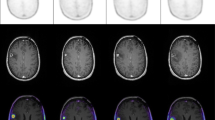

CGITA toolbox [30], using 11C-MET PET images and automatic extracted BTVs, allowed the extraction of 108 radiomics features for each selected metastasis. BTV segmentation examples are shown in Fig. 1. For predictive evaluation, 3 features (asphericity, low-intensity run emphasis, and complexity) were able to discriminate between responder and non-responder patients after feature reduction and selection. Precisely, asphericity is a measure of the deviation from a spherical shape, while the low-intensity run emphasis is a textural feature based on a grey level run (a set of consecutive, collinear voxels having the same grey level value). The length of the run is the number of voxels in one direction and reflects the size of texture elements [31]. The complexity refers to the visual information content of a texture. So, a texture is considered complex if the information content is high: this occurs when there are many patches in the texture with different average intensities [32]. Best performance in DA classification was obtained using the combination of the 3 selected features with sensitivity 81.23%, specificity 73.97%, precision (or positive predictive value) 82.94%, negative predictive value 71.95%, error 21.73% and accuracy 78.27%, compared to the use of all features. All results are shown in Table 1. Corresponding receiver operating characteristic (ROC) curves are shown in Fig. 2.

The fully automatic segmentation method

In the proposed method, PET images were pre-processed as previously described by our group [47]. Precisely, the body-weight SUV, the most widely used PET parameter, was used to convert PET images into SUV unit (g/ml) images. Successively, to obtain a fully automatic BTV segmentation system starting from the one proposed [27], our algorithm performs all segmentation steps automatically by individuating an optimal, operator-independent, initial ROI located around the tumour on an automatically selected PET slice. By taking advantage of the great sensitivity and specificity of 11C-MET radio-tracers in discriminating between healthy and tumour tissues, the system identifies the PET slice containing the maximum SUV (SUVmax) in the whole PET dataset avoiding any user intervention. Consequently, the SUVmax voxel is used as a target seed for a region growing segmentation [18] to automatically identify a ROI containing the lesion. It is worth noting that the region growing algorithm is used only to obtain a rough estimate of the lesion boundary. This initial operator-independent ROI is input to the next component of the system, an enhanced LAC segmentation algorithm [48], as extensively explained [27]. Despite the LAC method is able of locally widening or tightening around the lesion boundary, a stopping criterion has been implemented to prevent wrong segmentations when a free disease slice is reached. This because the LAC algorithm is driven by the image properties rather than by an inherent knowledge of whether the tumour is present. In other words, the LAC is automatically stopped when a free disease PET slice is reached [27]. In this way, the proposed system becomes fully automatic for the segmentation of brain metastases in 11C-MET PET images [29]. In the case of multiple brain metastases, each lesion is independently processed. A different local maximum (SUVmax-j, with j = 1:n) is identified for each lesion. By design, the first BTV contains global SUVmax. The delineation iterative procedure ends when the SUVmax of the currently processed lesion is less than 2 g/ml. However, the user will receive a warning message in case of multiple lesions and will be able to stop the process to avoid false-positive occurrences (healthy tissues with SUVmax > 2 g/ml).